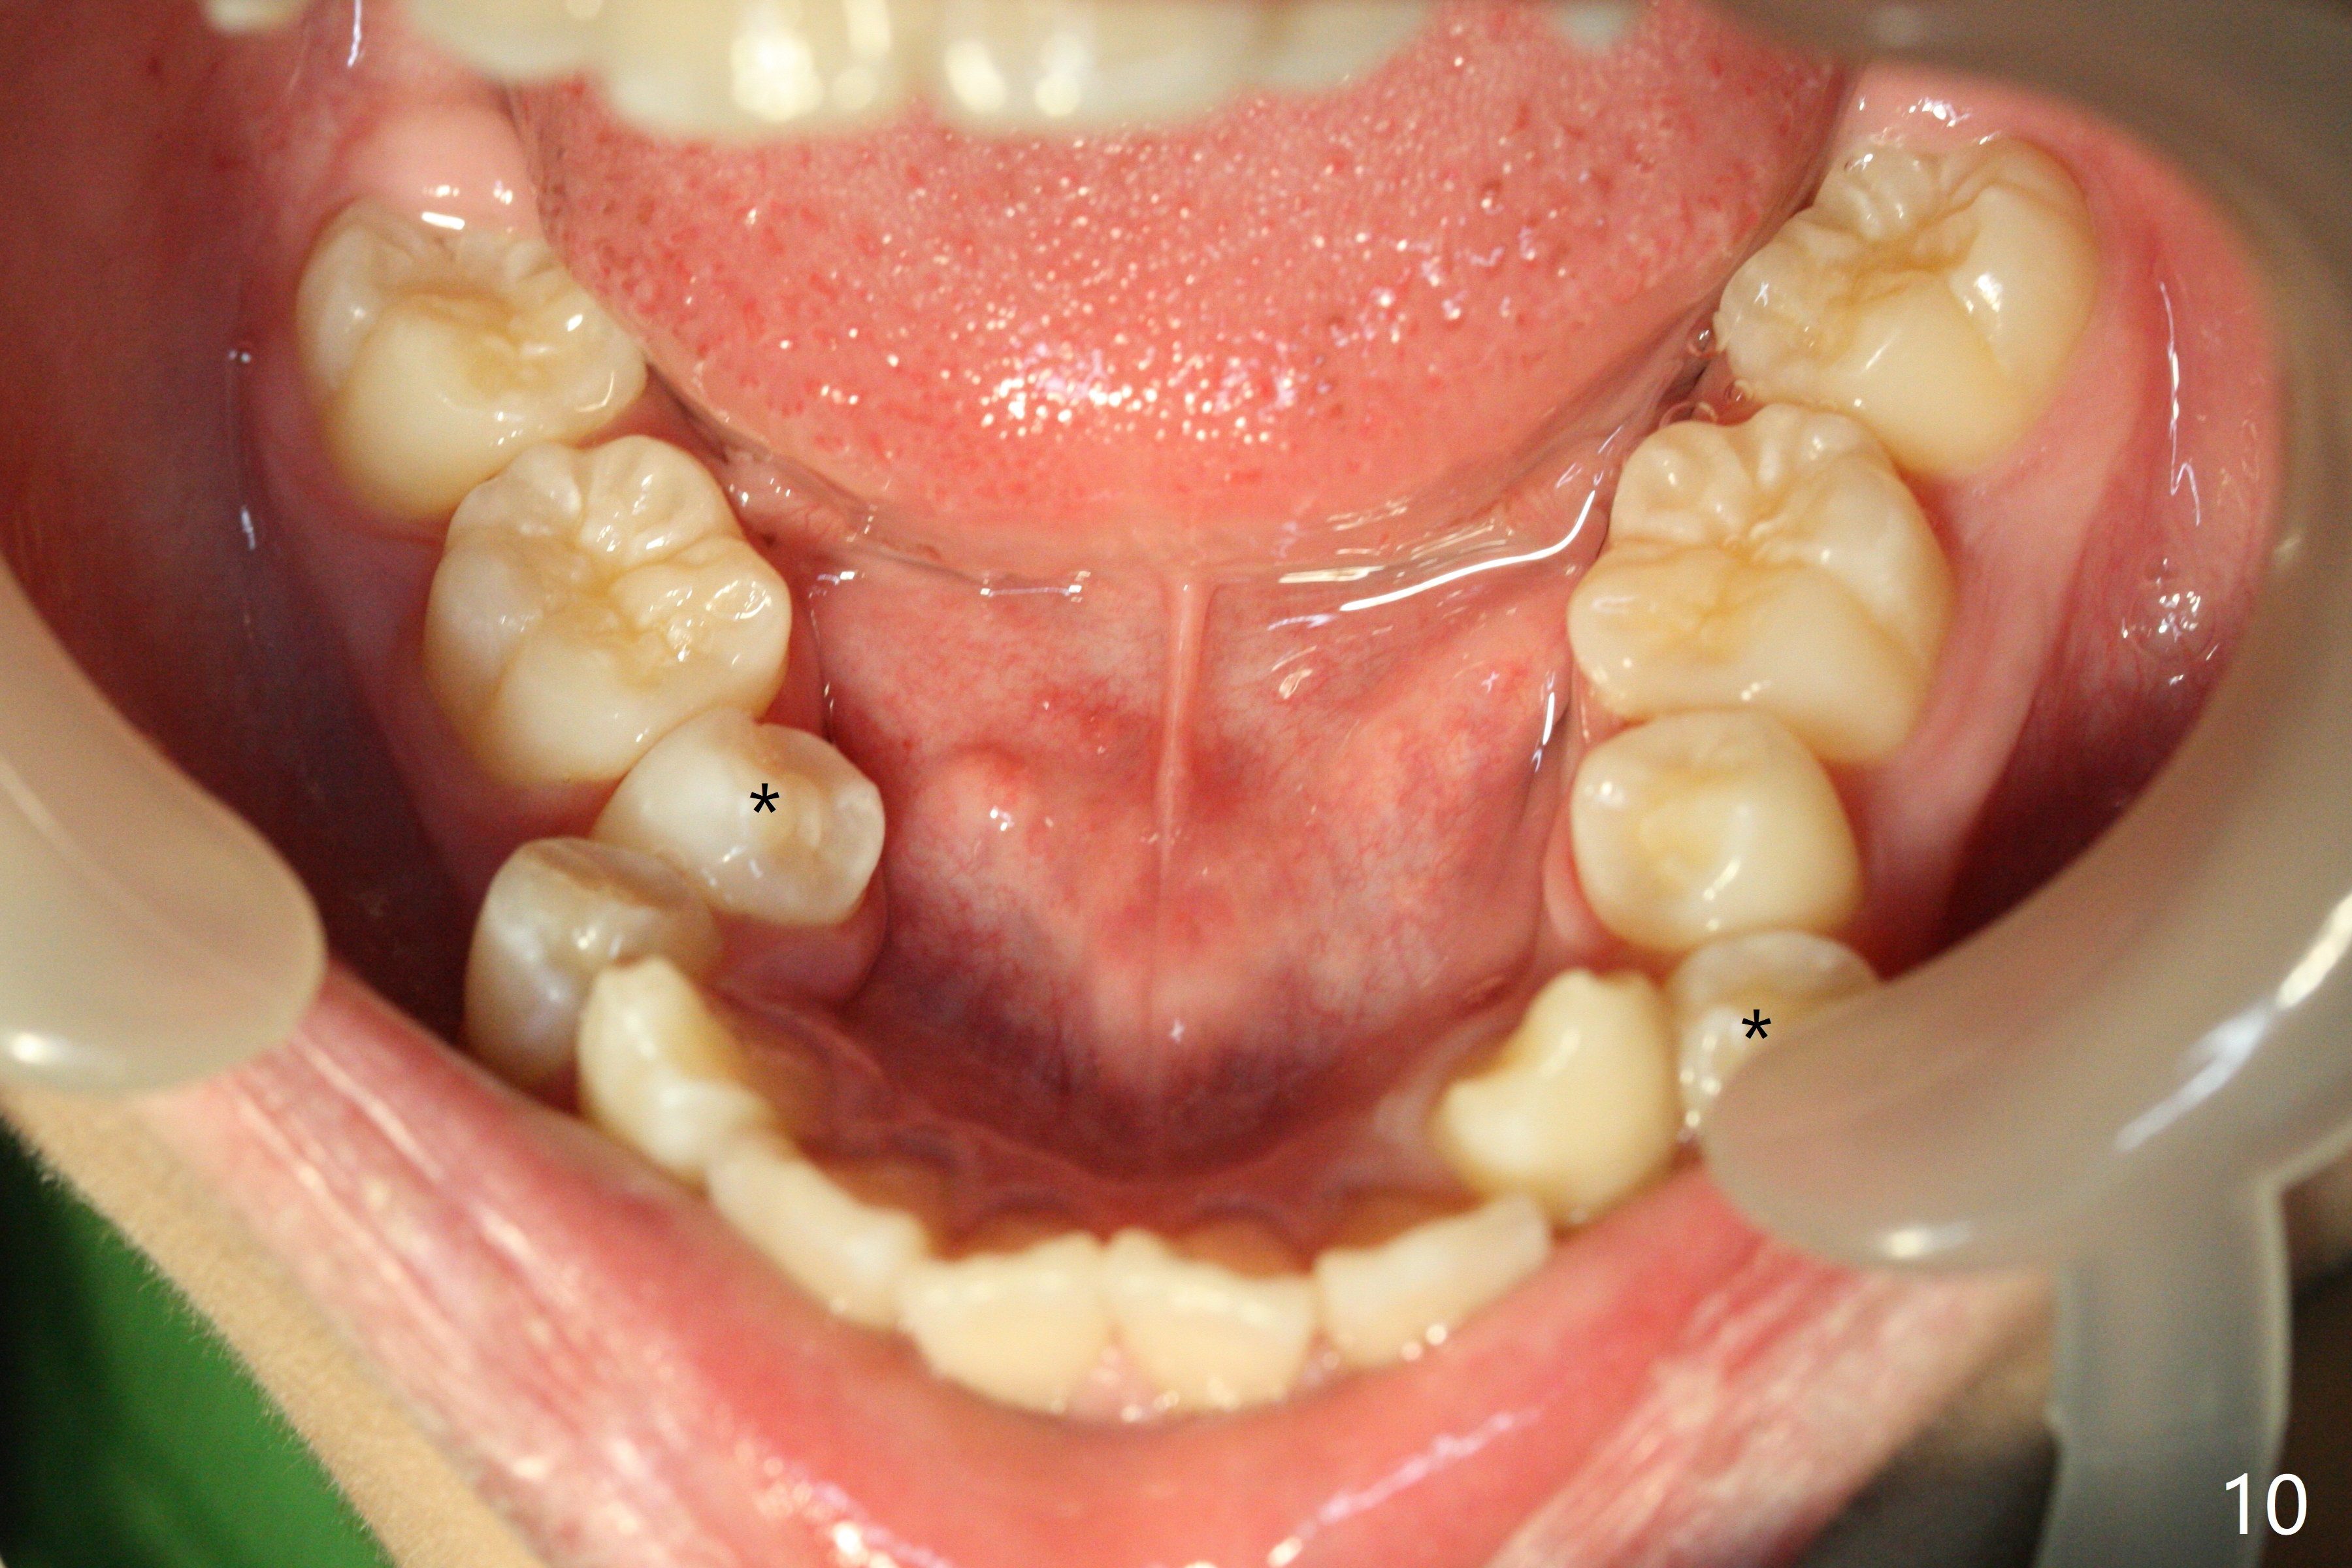

A 13-year-old man has protrusive lips (Fig.1,3,4) with upper midline deviation to the left (Fig.2).  Crowding is severe with LR5 severe lingual inclination (Fig.5,6,10).  To facilitate L6s' uprighting (Fig.10), LR5 and 3 of the 1st bicuspids will be extracted (Fig.6-8 x or *) and molar bands with lingual cleats will be used for the lower.  Cross arch molar retraction will be initiated immediately.  Open coil spring will be placed between UL1 and 3 with the 1st wires to correct the upper midline deviation and to gain the space for UL2.

The patient will return 2 months post extraction.  Shifting is expected to occur next to extraction sites (*) as indicated by arrows in Fig.9,11.  Take photos if it is the case.  Place bracket at UL2 if there is no space issue, but upside down (why?).  The most flexible wire is anticipated.  To establish Class I occlusion when wires are stiffer (18ss), LL5,6 will be mesialized as equally as LL3 distalized, while UL5,6 maintained basically in situ (Fig.11).  How to accomplish?